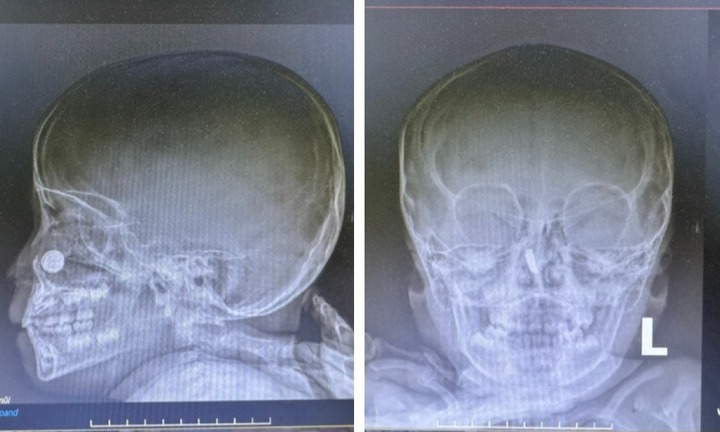

Bệnh viện Sản Nhi Nghệ An vừa tiếp nhận và can thiệp khẩn cấp cho một bệnh nhi 24 tháng tuổi bị bỏng sâu thực quản do nuốt phải pin cúc áo suốt 4 ngày.

Trong lúc chơi dưới nền nhà, bé trai một tuổi đã nhặt cục pin bỏ vào miệng ngậm, không may viên pin tuột thẳng xuống cổ họng.